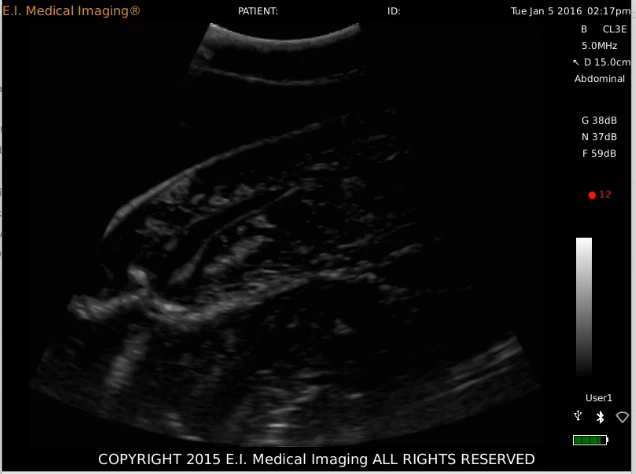

We willen weten of de haai zwanger is en in welk stadium van de zwangerschap ze verkeert. Op die manier kunnen we zien of ze op de Saba Bank pups krijgt, of dat ze de Saba Bank gebruikt voor voedsel tijdens de zwangerschap. Dit doen we door, net als bij mensen, een echografie te doen van de buik van de haai. Daar kun je op zien of de haai zwanger is of niet. Hieronder zie je de echo van een tijgerhaai.